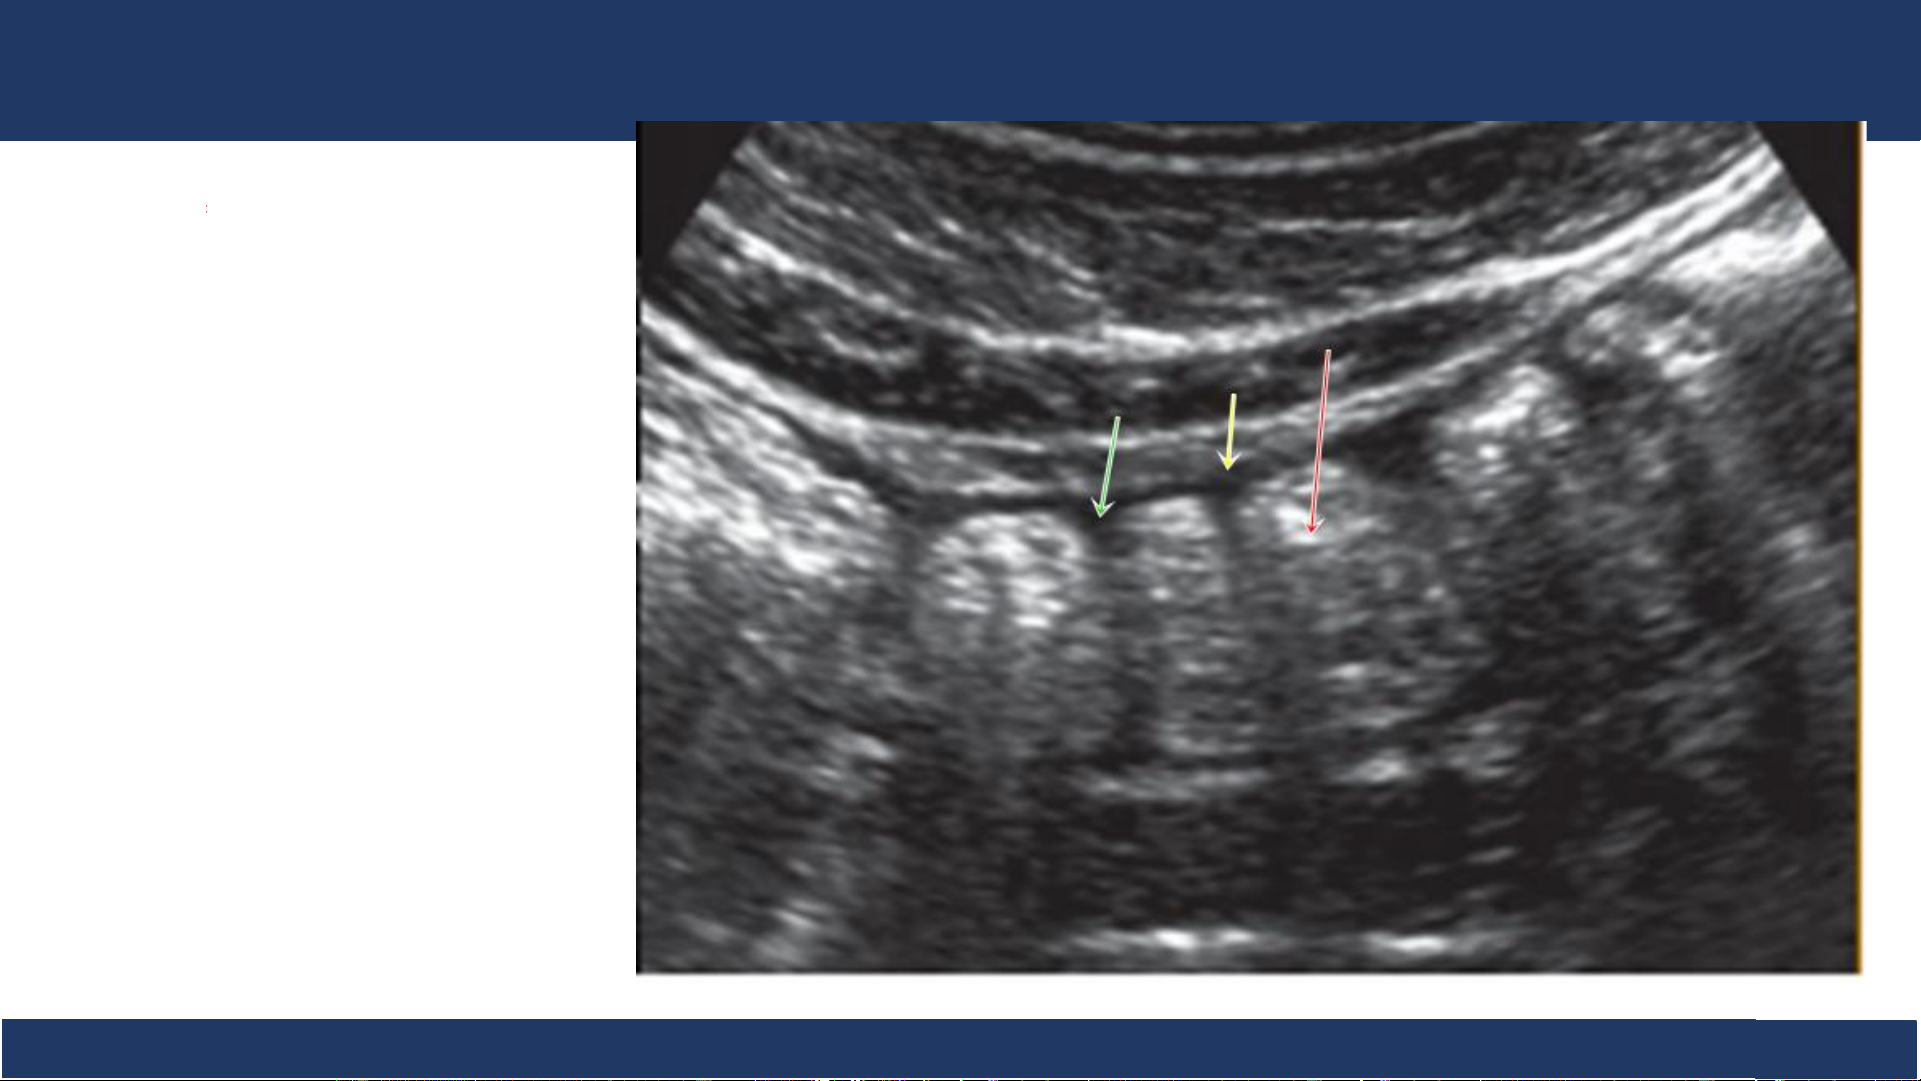

hình ảnh, ĐHYD TPHCM 17 SA: đại tràng Đại tràng . - Lòng chứa hơi (mũi tên đỏ) cho bóng lưng dơ) - Thành (mũi tên vàng) - Có nếp bán nguyệt (mũi tên xanh) Bệnh v B iệ ộ môn n Nh Chẩ i Đồng n đoán 1

hình ảnh, ĐHYD TPHCM 18 SA: đại tràng

Đại tràng quét ngang và dọc .

theo khung đại tràng, đi từ

manh tràng đến trực tràng.

+ Nhiều phân hơi, ít nhu động:

xếp thành từng ngấn ở ngoại

vi ổ bụng (đặc trưng trên mặt cắt dọc)

+ Nếp van hình bán nguyệt,

thưa thớt (nếu có nhu động) Bệnh v B iệ ộ môn n Nh Chẩ i Đồng n đoán 1